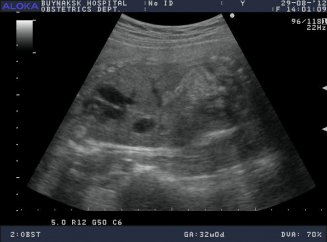

УЗД діагностика в першому триместрі вагітності формує загальне уявлення про розвиток плода. Перше дослідження проводиться з 11 по 14 тиждень, але виникають ситуації, коли потрібно рання діагностика для підтвердження вагітності та життєдіяльності малюка. У цьому випадку важливим показником вважається серцебиття дитини , Яке можна прослухати на певному тижні, а на який саме ви дізнаєтеся нижче.

Серцебиття плоду не регулюється нервовою системою і ніяк з нею не взаємопов'язане. Залежить це можливо через недорозвиненість нервової тканини. Майбутня мама, вирушаючи на позачергове раннє УЗД, задається питанням, а коли з'являється серцевий стукіт і чи зможе вона його прослухати на цьому тижні . Відповідь на ці сумніви досить простий. Побачити перший стук серця на моніторі можна, починаючи з 6 тижні , Почути його можливо на тиждень раніше (залежить від потужності ультразвукового устаткування).

Серцебиття плоду з'являється рано, прослухати його можна на 5-6 тижні, а якщо обстеження проводиться за допомогою сучасних трансвагинальних датчиків , То подібний захід цілком ймовірно і на 4 тижні.